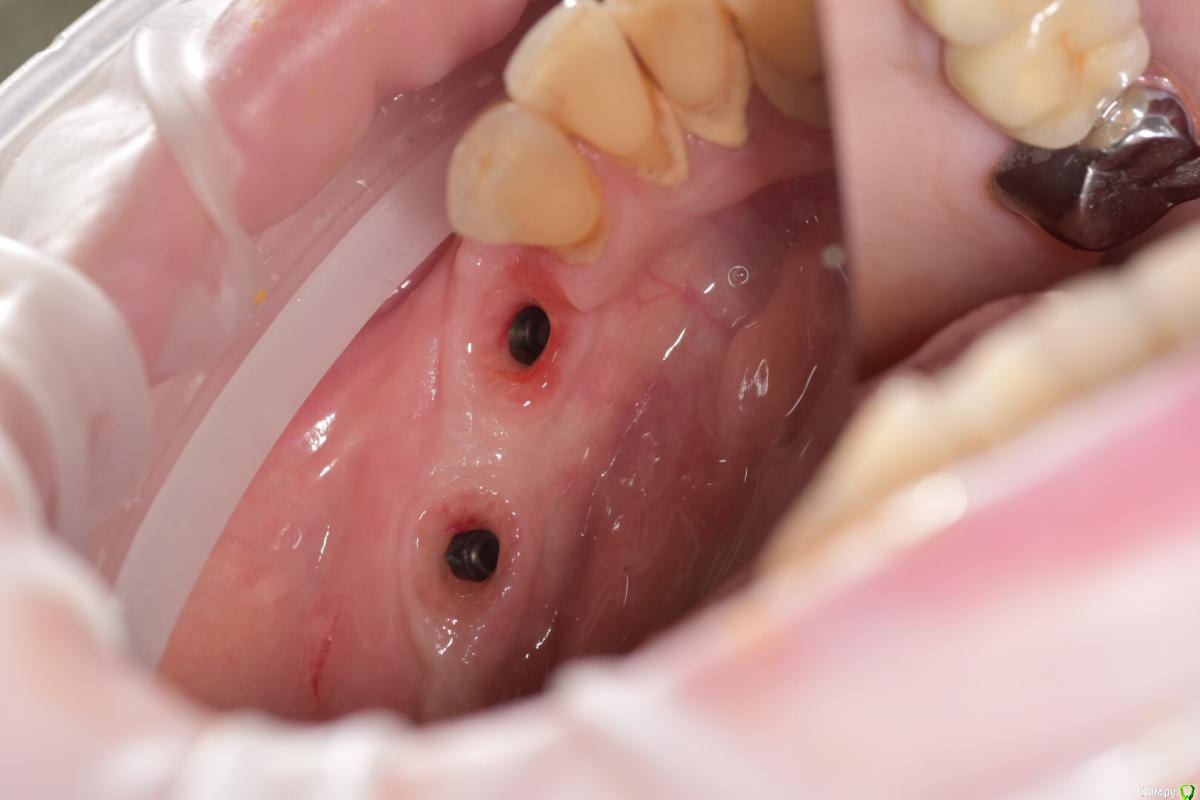

Santi Опубликовано 18 сентября, 2018 Поделиться Опубликовано 18 сентября, 2018 Имеем Концевые деффекты н/ч. Справа по плану НКР+импланты в позициях 4-6, слева импланты+ десна Итог сразу после Через 5-6 месяцев имеем такую картину Сразу после мягкотканной пластики И через пару месяцев Заранее пардоньте за качество фото и отсутствие картины ДО Ваше мнение коллеги ? 3 Ссылка на комментарий

Santi Опубликовано 19 сентября, 2018 Автор Поделиться Опубликовано 19 сентября, 2018 Этапов аугументации к сожалению нету. То , что выложил + этап раскрытия Ссылка на комментарий